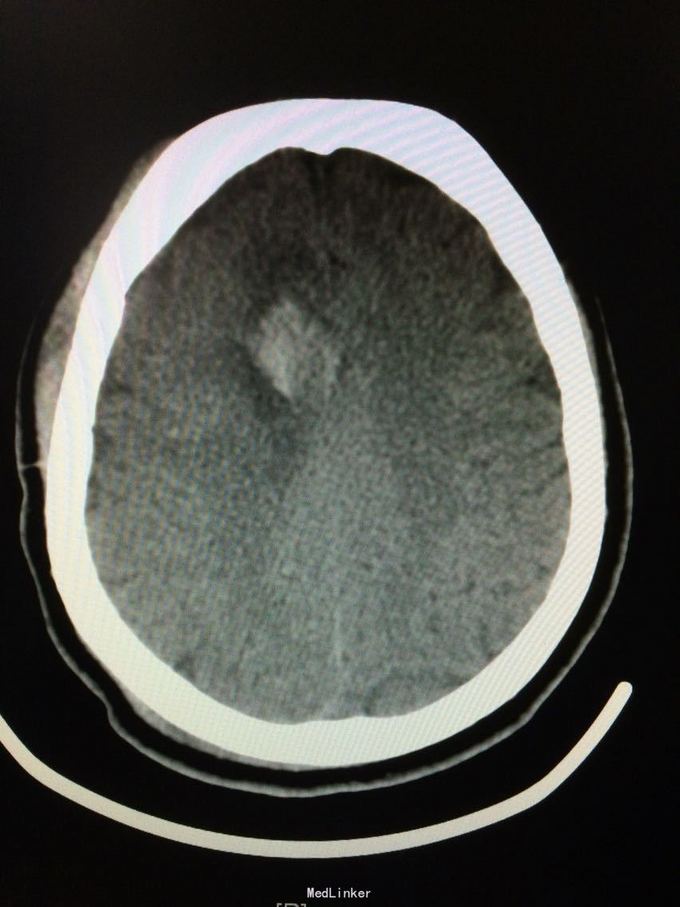

主诉:记忆力减退3月,左侧肢体乏力3天 病史:患者51岁女性,3月前无明显诱因出现记忆力减退,伴头痛,3天前出现站立不稳,左侧肢体乏力,步行困难,当地CT提示右侧额叶低密度灶,

查体:左侧上肢肌力4级,右侧5级,轻瘫试验左侧阳性 辅助检查:右侧额叶、胼胝体膝部病变伴出血,增强扫描明显强化。考虑胶质瘤

诊断:右侧额叶多发脑软化灶 处理:全麻下行右侧额叶占位病变切除术,术后病理提示:符合脑软化,未见明显肿瘤因素等